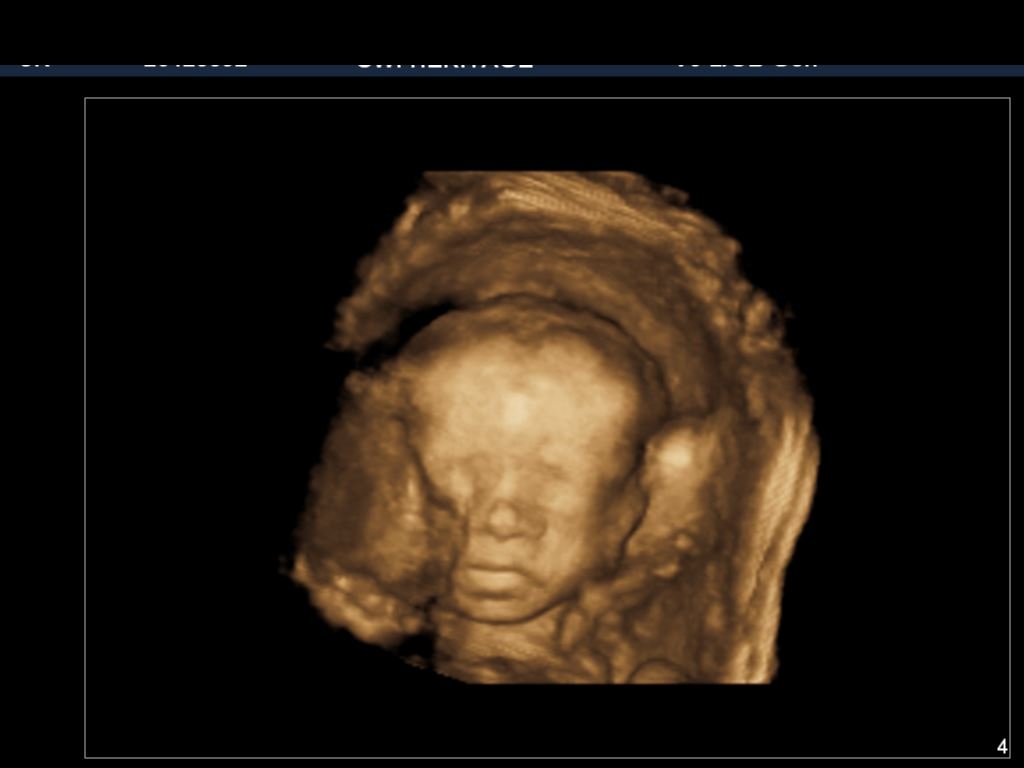

• Went for my appointment yesterday,  everything looks just fine and also had 3d ultrasound scheduled but they said 28 weeks would be good for better pics. In week 26 now so have to wait for 2 weeks more.   :)

• @sonalisharma yes, it is better to wait I’ll 28 -32 weeks because then they have some fat on them, otherwise you end up with creepy alien photos. haha. Since I have to have growth US every 4 weeks due to my weight, I ask to see her in 3D since they have the capability... and because I'm paying an arm and a leg (what a weird phrase when you write it out), I figure why not see my little alien. haha Also, thank you. I'll update whenever I know something. The nurse I talked to yesterday said that if there was a problem that the radiologist will call them but if there isn't a problem then they'll just send a report over. So who knows when I'll know if something is ok.